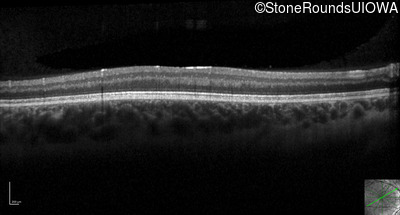

Optical Coherence Tomography - Left - 10/200 sc

Exemplar / OCT Stack

OCT Stack